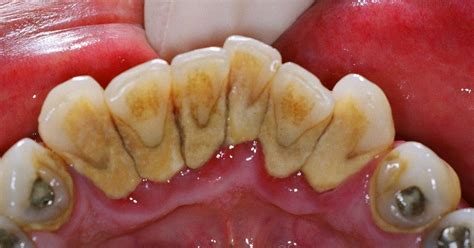

Acumulación de sarro en los dientes inferiores.

El sarro, también conocido como cálculo dental o tártaro, es un problema bucodental muy frecuente, aunque muchas personas no le dan demasiada importancia. Consiste básicamente en la calcificación de la placa bacteriana, o placa dental.

El sarro dental es una capa de suciedad y residuos calcificados que se acumula en los dientes como consecuencia de una higiene oral insuficiente o ineficiente. Esta capa de suciedad también se puede amontonar en el borde o debajo de las encías, llegando a irritar los tejidos gingivales.

Una vez que esta película de restos se calcifica y endurece, precisamos de ayuda profesional para su eliminación -limpieza con ultrasonidos, curetas, etc.-. El sarro se distingue por su color, que puede ir de blanquecino a pardo. Además los problemas estéticos derivados de su aspecto desagradable, su presencia puede traer consecuencias negativas para la salud oral.